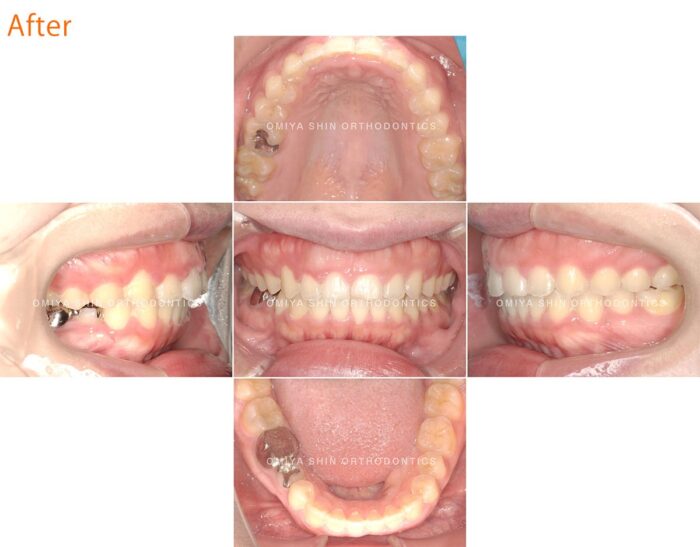

こちらが治療を始めて半年後のお口の中の状態です。患者さまの1番の悩みだった「前歯の隙間」は改善されています。

しかし、上下の正中(前歯の中心)が揃っていない(画像2)ことと、奥歯のかみ合わせが不十分(画像1,3)なため、再度マウスピースを作成し、調整を行いました。

治療後の変化

- 見た目のコンプレックスがなくなり、人前で自然に笑えるようになった

- サ行・タ行の発音がクリアになり、話しやすくなった

- 食事中に食べ物が詰まりにくくなった

正中離開(すきっ歯)は放置しても自然に治ることはほとんどありません。この症例のように、マウスピースで時間をかけて歯列を矯正することで、見た目だけでなくかみ合わせも改善されれば、後戻りの心配がありません。